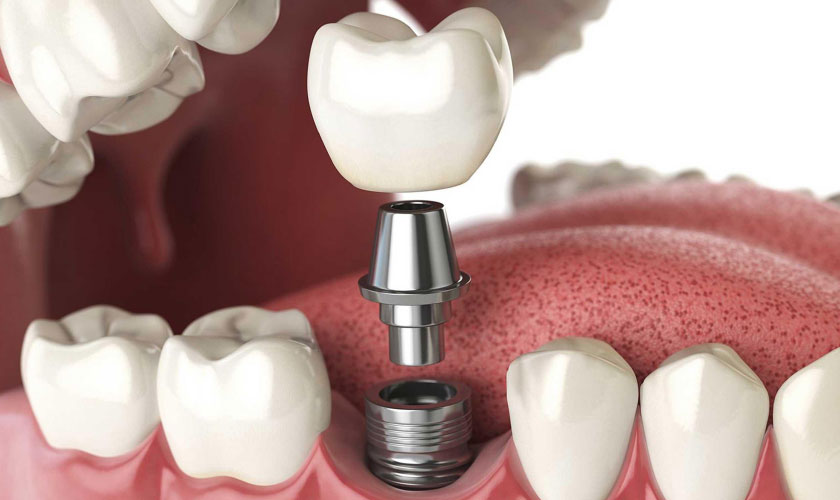

Implant là trụ cấu thành từ Titanium, được cấy vào xương hàm nhằm mục đích thay thế chân răng đã mất. Sau thời gian lành thương và implant đã tích hợp vào xương, Bác sĩ sẽ tiến hành gắn răng sứ trên implant để tạo thành một chiếc răng hoàn chỉnh nhất.